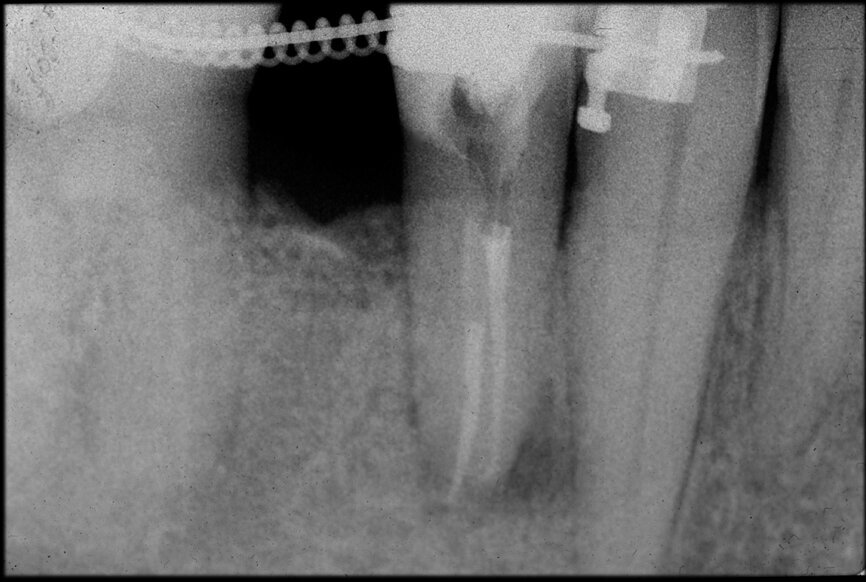

Preoperative CBCT evaluation is useful in cases requiring a surgical approach, not only in order to confirm the presence of a lesion but also to plan the procedure and, in particular, identify the type of surgical incision to be used, based on its size and location (Figs. 23–25). This specific case is characteristic of this situation. The intraoral radiograph did not make it possible to ascertain the extent of the lesion, which involved not only the apical region of the premolar but also a distal edentulous segment. This region would need to be treated with regenerative therapy in order to guarantee correct healing of the area, with subsequent insertion of a membrane, the flap must be protected using a totally different approach to that required for endodontic surgery. The intraoperative images illustrate the various stages of the procedure (Figs. 26–28). The CBCT scan performed 12 months later confirmed complete healing of the apical lesion and perfect graft integration (Figs. 29–31).